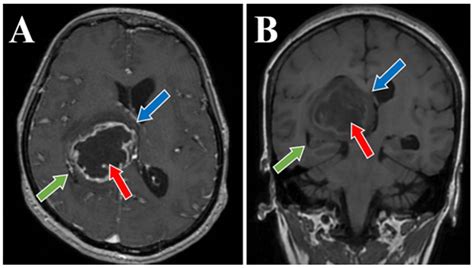

The journey toward a formal diagnosis usually begins with a neurological examination followed by advanced imaging. Physicians rely on several diagnostic tools to map the tumor’s size, location, and relationship to vital brain structures. Magnetic Resonance Imaging (MRI) with contrast remains the gold standard for visualizing these growths. In many cases, specialized sequences such as spectroscopy or perfusion imaging are used to differentiate between tumor tissue and postoperative changes.

The primary objective is maximal safe resection. Surgeons utilize neuronavigation systems and intraoperative MRI to remove as much of the tumor as possible. Even when total removal isn’t possible, “debulking” the tumor can alleviate intracranial pressure and improve the efficacy of subsequent therapies.

• high grade glioma MRI